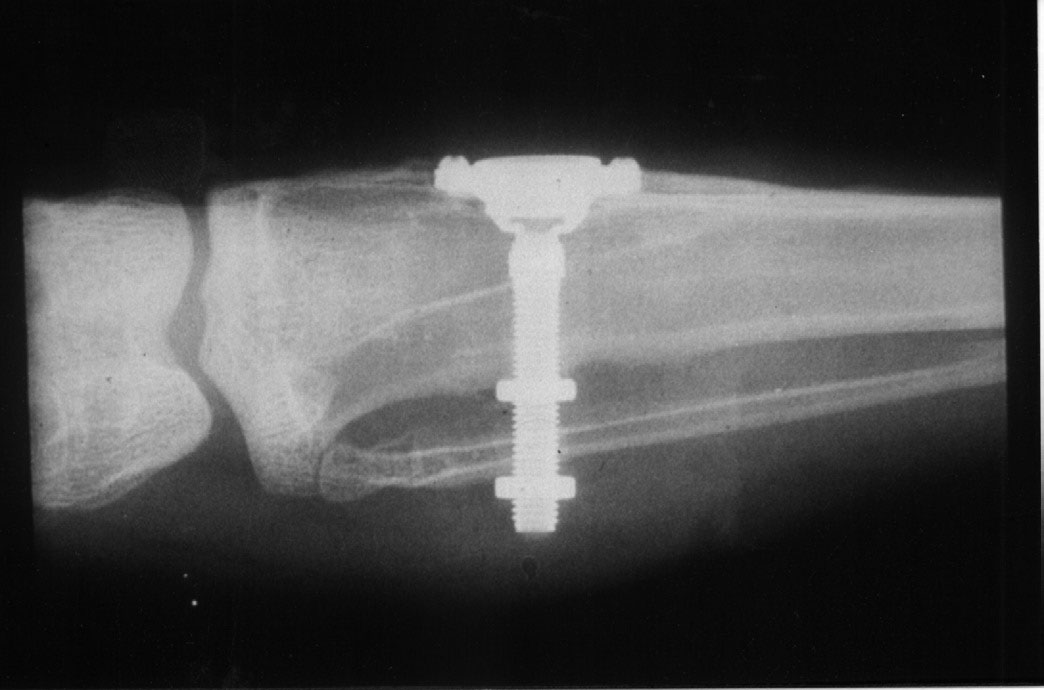

Almost 25 years later in 1968, a new dental implant concept called the transosseous implant was introduced by Small. The name was derived from the fact that it transversed the mandible from the bottom to the top.8 This implant was inserted underneath the chin. A flat bone plate was fixed under the skin against the inferior border of the mandible. Several threaded posts projected into the anterior mandible from the plate. Two to four of the posts went completely through the mucosa and into the oral cavity to help fixate the denture prosthesis. Transosseous implants were machined from titanium, or a gold alloy. There were several disadvantages to this implant system. This procedure was performed under general anesthesia in a hospital setting and was quite invasive. Another downside was frequent bone loss around the posts with bleeding on probing. Studies showed that this design had a success rate of 91% after 10 to 16 years of function, but it was not a healthy environment.9 This implant design is no longer used today and was replaced by the endosseous implant.